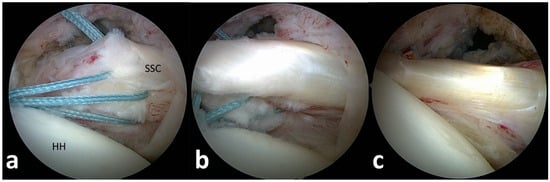

On postoperative MRI scans, subscapularis tendon repair integrity was graded on axial T2-weighted images using the Sugaya classification, with types 1, 2 and 3 graded as intact tendons (Figure 1a) and types 4 and 5 with tendon discontinuity graded as a retear [20,21]. Subscapularis muscle atrophy was evaluated on the Y-shaped view in the sagittal plane: no atrophy (grade 0), mild atrophy (grade 1), moderate atrophy (grade 2) and advanced atrophy (grade 3) (Figure 1b,c). The MRI scans were graded separately by two investigators (CB and SP) and in consensus in case of discrepancy.

Subscapularis muscle atrophy grading on the sagittal MRI scans in the ARG group showed no or mild atrophy (grade 0 or 1) in 13 cases (72%) and moderate atrophy (grade 2) in 5 cases. In the ORG, no or mild atrophy was present in 11 cases (69%) and moderate atrophy in 5 cases (Figure 1b,c; Table 3).

Figure 1. (ac). Postoperative subscapularis imaging. (a) Intact subscapularis tendon in the axial plane (Sugaya type 1). (b) Subscapularis muscle with no atrophy (y-shaped plane). (c) Advanced subscapularis atrophy of the upper muscle portion.